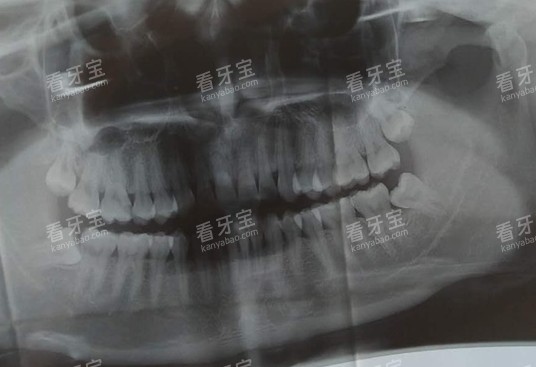

- 等炎症消了之后,拍个牙片看看智齿的位置,如果智齿长歪了、反复发炎,建议拔掉。现在拔智齿大多是小切口操作,创伤小,修养时间短,不用太害怕。